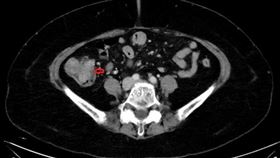

不吃瀉藥無法大便 原因竟是「太窄」

北部一名老先生長年排便不順,經常出血,近年嚴重到不吃...

她排便習慣改變 竟發現第3期大腸癌

和許多大腸癌患者一樣,北部一名中年婦人發現自己解便異...